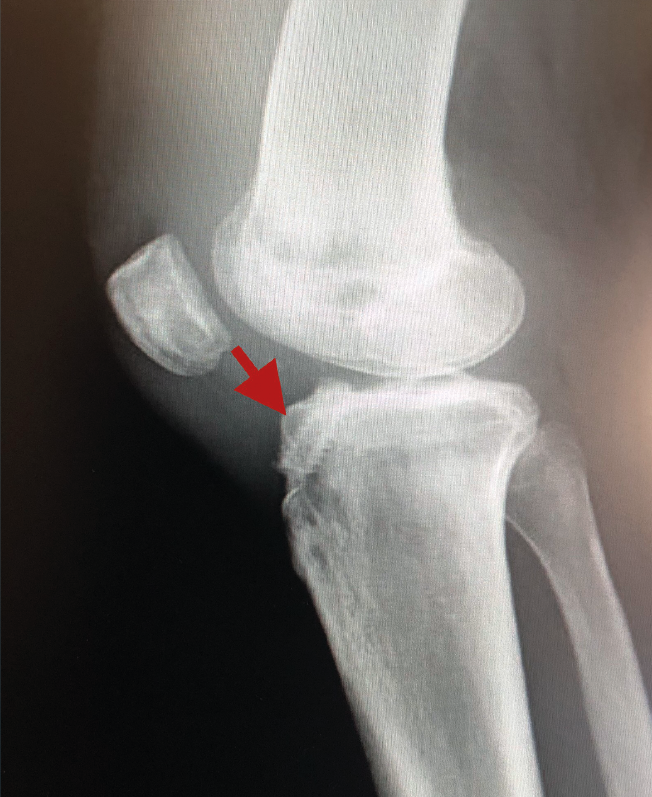

Figura 1. Laxitud en el cajón anterior. Radiología forzada.

Desde el punto de vista clínico, se consideran motivo de revisión quirúrgica aquellos casos en los que exista un desplazamiento anterior comparado con el contralateral mayor de 5 mm, pivot shift de alto grado, dolor, inflamación, sensación subjetiva de inestabilidad y limitación funcional para las actividades de la vida diaria o deportiva(9,10). Algunos autores han rebajado esta cifra a 3 mm con respecto a la rodilla contralateral o 10 mm de desplazamiento absoluto en el plano sagital(11)(Figura 1).